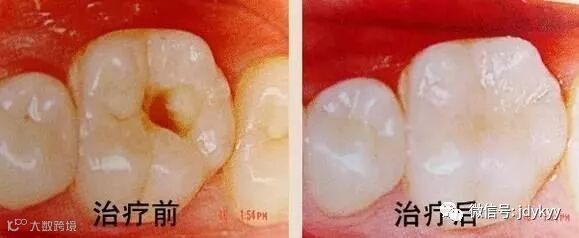

银汞合金充填术

对已形成实质性缺损的牙齿,充填术是目前成效较好的方法。